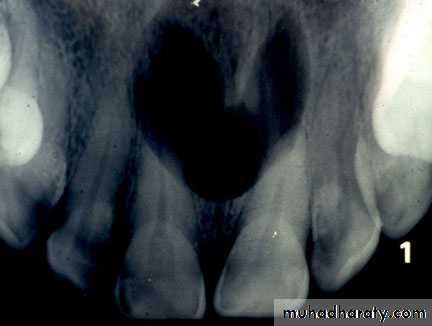

Nasopalatine duct cyst

Which form in the midline of the anterior maxilla, un common.Nasopalaine, incisive canal, medianpalatine, median alveolar cysts are variants of the same lesion.

Slowly growing, occasionally they cause intermittent discharge with salty taste.

Large cyst may cause swelling in the midline of the anterior palate.

When it is superficial called palatine papilla cyst.

Radiograph shows a rounded radiolucent area with well defined sclerotic margin in the anterior part of the midline of the maxilla.

They occasionally appear heart-shaped because of radiographic superimposition of the nasal spine.

They are usually symmetrical but may be larger to one side.